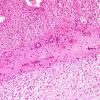

13C4 Lymphoma, IV, T-NK type (Case 13) H&E 4x